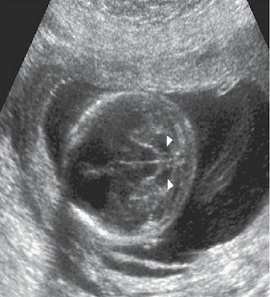

【107-2 醫學(六) 第29題】子宮內膜會受荷爾蒙之影響而於超音波掃描下有所變化,下圖中那個超音波圖形,其內膜之變化顯示患者目前之生理情況,最接近於排卵日?

詳解

破題關鍵

這題的解題核心在於辨識子宮內膜在排卵期特有的「三線徵」(triple-line sign),圖片 C 清楚呈現了這個特徵。

選項拆解